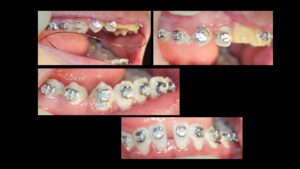

臼歯関係は、右が 4㎜ II級。左が 7㎜ II級で、7番しか咬合しておらず、著しい開咬を呈していました。

8歳からリンガルアーチで拡大を開始し、3年間拡大を続け、12歳でマルチブラケットを付けて治療を開始したそうですが、開咬が治らないためにアンカースクリューを4本打って治療を続けたとのことです。

こんなスクリューじゃあ何の意味もありません。

まさにやっている事がデタラメです。

ひろ矯正歯科に来られた時には、口腔内清掃状態は悪く、全ての歯が齲蝕でボロボロ、要治療でした。

治療中はブラッシング指導は一切無かったそうです。